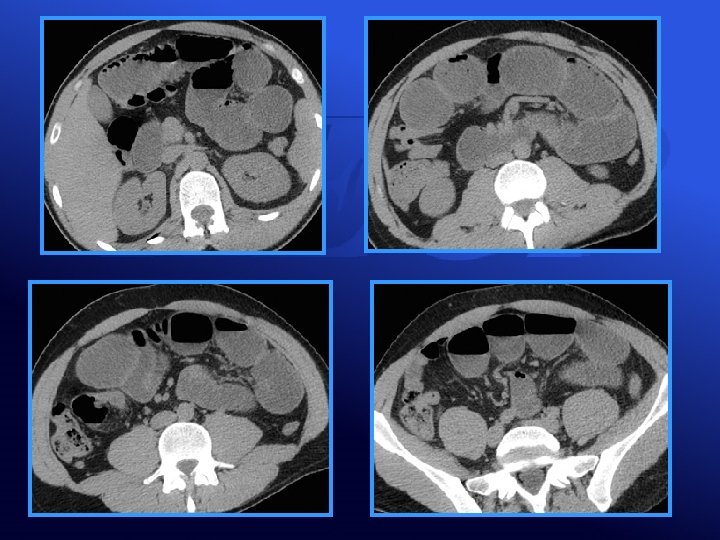

PNEUMATOSE PARIETALE: ISCHEMIE DU GRÊLE

Cas Clinique n° 4 • Madame L. , 90 ans douleur abdominale Abdomen souple • Etat général conservé

Pneumatose: ischémie mésentérique? • POUR • Imagerie • CONTRE • Clinique • Absence de facteur de risque